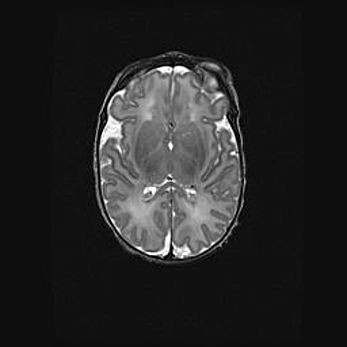

Множественные кисты обоих полушарий головного мозга, наибольшая из них в правой затылочной области. Ассиметричная атрофическая гидроцефалия.

Возраст: 7 месяцев

Вес: 5660 г

Пол: мужской

Окружность головы: 41,5 см

Срок гестации: 28-29 недель

Кисты головного мозга развиваются в результате многоочаговых некрозов вещества мозга и возникают вследствие перенесенной перинатальной инфекции, менингитов, энцефалитов, асфиксии, родовой травмы, расстройств мозгового кровообращения различного генеза. Образованию кист в веществе головного мозга плодов и новорожденных способствуют такие факторы, как высокое содержание в нем воды, недостаточная (или отсутствие) миелинизация и слабая астроглиальная реакция на повреждение.

Кисты могут сочетаться с гидроцефалией и другими поражениями головного мозга.